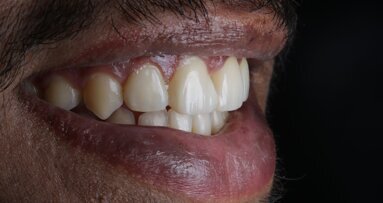

Vanini described an anatomical stratification technique that goes beyond the typical three dimensions (hue, chroma, value) of color. The technique, especially useful when esthetic demands are high, enables dentists to predictably create life-like esthetic restorations that are indistinguishable from natural teeth. [1, 2]

A 10-year-old male patient reported with a complaint of trauma to the upper left central and lateral incisors, involving the enamel and dentin. Direct composite was used in multi-layers and the smile was restored. This article explains detailed steps in the polychromatic layering technique with special emphasis on the finishing and polishing protocol. 3M Espe Filtex Z350 Xt was used with a universal bonding agent.

Fig 31-41: Polishing protocol and post-op

The article demonstrates how using the right protocols and armamentarium for composite materials can give life-like results in a short time in a minimally invasive way. No single layering technique can ensure a 100% success rate. Regardless of the technique, establishing good secondary and tertiary anatomy and thorough polishing are the key steps that make a restoration look more natural. Composite is the perfect material for allowing correction of mistakes or improvement.